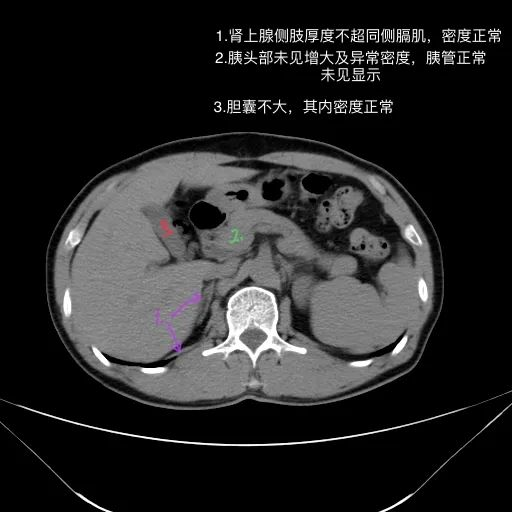

影像描述:

肝脏缩小,包膜凹凸不平,肝裂增宽,各叶比例失衡,肝实质密度不均,肝S4小片低密度影,约cm;胆囊不大,其内未见异常密度影,胆道系统未见扩张;胰腺、脾脏形态、密度、大小未见异常;双肾上腺及双肾形态、密度、大小未见异常,双输尿管未见扩张,膀胱充盈良好,壁光滑,其内未见异常密度影;前列腺未见异常;胃肠道未见充盈,壁未见明确增厚,食管胃底多发迂曲、增粗血管,腹部及腹膜后未见肿大淋巴结;腹水。

影像诊断:

1.肝硬化失代偿表现(腹水,食管胃底静脉曲张)。

2.肝S4小片低密度影,建议复查或进一步检查。